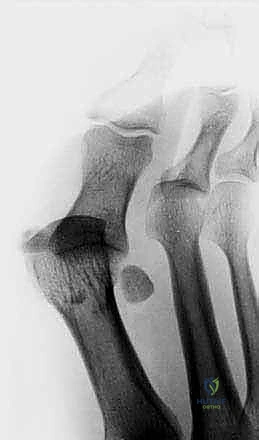

2. التصوير بالأشعة السينية (X-Rays)

يتم إجراء صور أشعة سينية بوضعيات تحمل الوزن (Weight-bearing) وبوضعيات الإجهاد (Stress views). تساعد الأشعة السينية في:

* استبعاد وجود كسور في عظام المشط أو السلاميات.

* تقييم العظام السمسمانية (البحث عن كسور أو هجرة غير طبيعية للعظام السمسمانية، مما يدل على تمزق الصفيحة).

* تقييم تضيق المسافة المفصلية.